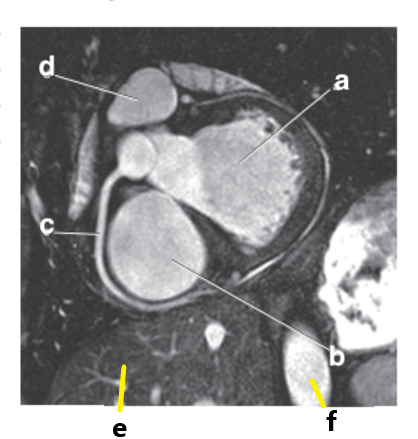

What is letter b ?

Left ventricle

What is letter a ?

Left atrium

Right ventricle

What is letter h ?

What is letter d ?